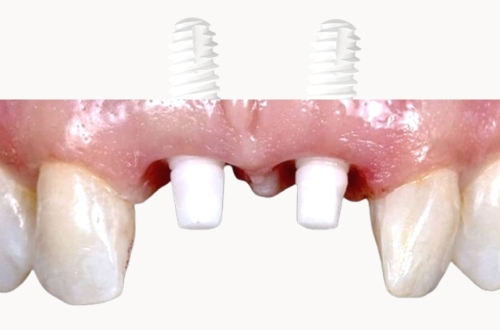

IMPLANTATE AUS KERAMIK

Vorteile: natürliche Ästhetik, Biokompatibilität, Langlebigkeit, Stabilität, Zahnfleischfreundlichkeit und Knochenfreundlichkeit.

Seit mehr als 15 Jahren verwenden wir in der Tagesklinik ausschließlich Implantate aus Keramik.

- Natürliche Ästhetik: Implantate aus Keramik sehen aus wie natürliche Zähne und harmonieren perfekt mit dem restlichen Gebiss. Sie bieten eine ästhetisch ansprechende Lösung für den Zahnersatz.

- Biokompatibilität und Allergiefreiheit: Keramikimplantate sind biokompatibel, was bedeutet, dass sie gut vom Körper vertragen werden. Im Gegensatz zu Metallimplantaten verursachen sie keine allergischen Reaktionen oder Unverträglichkeiten.

- Langlebigkeit und Stabilität: Implantate sind äußerst haltbar und können bei guter Pflege ein Leben lang halten. Sie bieten eine stabile Grundlage für Zahnprothesen, Kronen oder Brücken und gewährleisten so eine zuverlässige Funktion.

- Zahnfleischfreundlichkeit: Implantate aus Keramik zeichnen sich durch ihre zahnfleischfreundlichen Eigenschaften aus. Sie verursachen keine Reizungen oder Entzündungen des Zahnfleischs und fördern so eine optimale Mundgesundheit.

- Knochenfreundlichkeit: Implantate aus Keramik unterstützen den Knochenabbau nicht. Im Gegenteil, sie fördern die Knochenintegration und stimulieren das Knochenwachstum, was langfristig die Stabilität des Kieferknochens gewährleistet